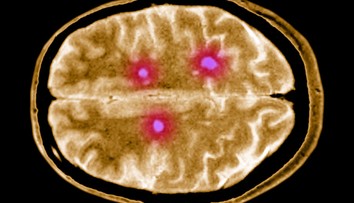

Ilustračná snímka Zdroj: Profimedia

Roztrúsená skleróza patrí medzi najzákernejšie ochorenia nervového systému. Postihuje najmä mladých dospelých a spôsobuje postupnú stratu pohyblivosti či reči.

Vedcom z britskej univerzity v Cambridge sa teraz podarilo urobiť prelomový objav – identifikovali špecifické mozgové bunky, ktoré by mohli vysvetliť, prečo choroba postupuje aj napriek liečbe.

Tím vedcov z v spolupráci s americkým Národným ústavom pre starnutie (NIA) objavil vzácny typ mozgových buniek označovaný ako DARG (disease-associated radial glia-like). U pacientov s progresívnou formou roztrúsenej sklerózy sa tieto bunky vyskytujú až šesťkrát častejšie než u zdravých ľudí.

Podľa štúdie publikovanej v prestížnom časopise Neuron DARG bunky spúšťajú zápal a urýchľujú poškodzovanie mozgového tkaniva. Vedci zistili, že vznikajú z nervových kmeňových buniek, ktoré sa akoby vracajú do vývojovo skorého štádia, no namiesto obnovy mozgu začnú starnúť a vylučovať látky, ktoré poškodzujú okolité bunky.

Pri analýze mozgových tkanív pacientov vedci zistili, že DARG bunky sa nachádzajú práve v oblastiach najväčšieho poškodenia. Ležia v tesnej blízkosti imunitných buniek a pravdepodobne slúžia ako ich „spúšťač“ – udržiavajú chronický zápal, ktorý mozog dlhodobo ničí, uvádza magazín Neuroscience News.